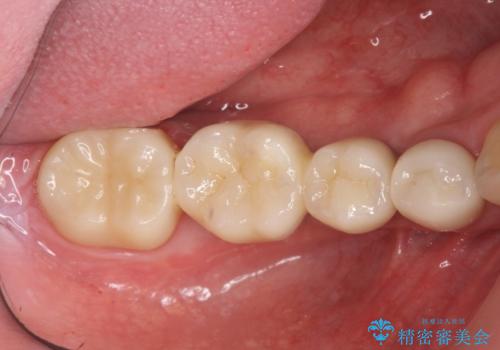

銀歯だらけの口の中を改善したい

- 80万円(ストローマンインプラント×2・チタンカスタムアバットメント×2・ジルコニアクラウン×4)費用は治療当時の料金となります

インプラントを用いることで残っている歯の負担も減らし、長期的な予後を見込むことができます。